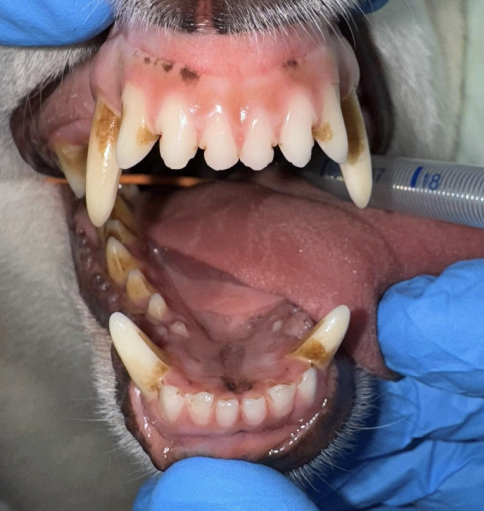

・Before

歯石の沈着と口臭を気にされていました。

歯磨きも挑戦されているようですが、うまく磨けず歯石がついている状態でした。

特に奥歯に歯石がついており、一部赤みや腫れている部分も認められました。